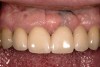

Figure 4  View of the completed central and lateral incisor with margins placed subgingivally, but maintaining tissue health.

Figure 4

The most common reasons to extend a margin below tissue are: caries below gingiva; old restorations that already exist below gingiva; to achieve adequate tooth preparation length for proper retention and resistance; to make significant contour alterations; to hide the margin when the tooth is discolored (Figure 3 and Figure 4); and to hide the margin when the restorative material of choice demonstrates optical properties different from those of the natural tooth such that the margin would be highly visible. Regardless of why a subgingival margin is chosen, there are 2 negative responses that may occur.